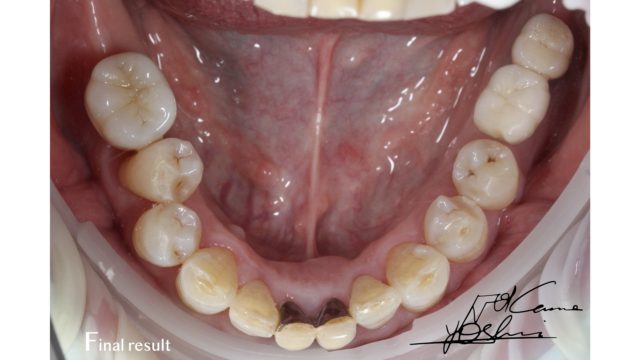

お口の下部、AFTER写真です。